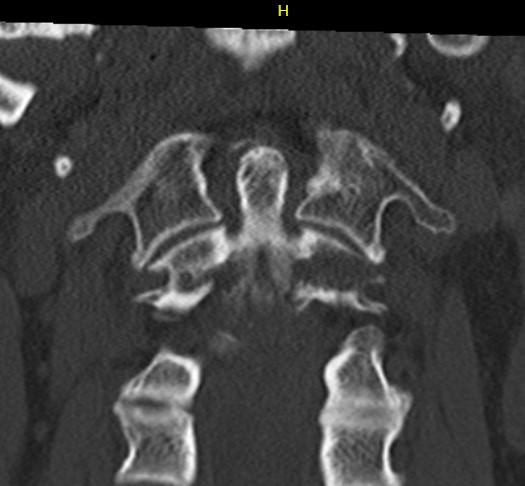

Bilateral pars fracture of C2

Traumatic spondylolisthesis of C2

CT scan